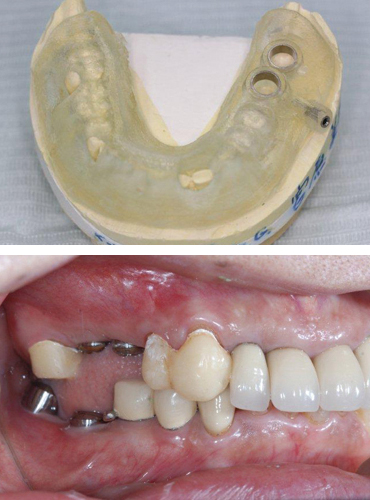

患者さんのCTスキャンデータをもとに、非常に精度の高いサージカルテンプレートが作製でき、より安全性に優れたインプラント埋入を可能にします。

このサージカルテンプレートとノーベルガイド専用外科キットを使用したガイディッド・サージェリーは、低侵襲のフラップレス術式を可能にし、患者負担を軽減します。また、事前に補綴物を作製することができるため、患者さんはインプラントを埋入した日に新しく機能する歯を手に入れることができます。

ガイデットサージェリーとは、CTの情報をもとにコンピューター3Dシミュレーション(ノーベルガイド)を行い、手術用のテンプレート(サージカルテンプレート)を装着し手術することです。

サージカルガイドによるガイデッドサージェリー手術